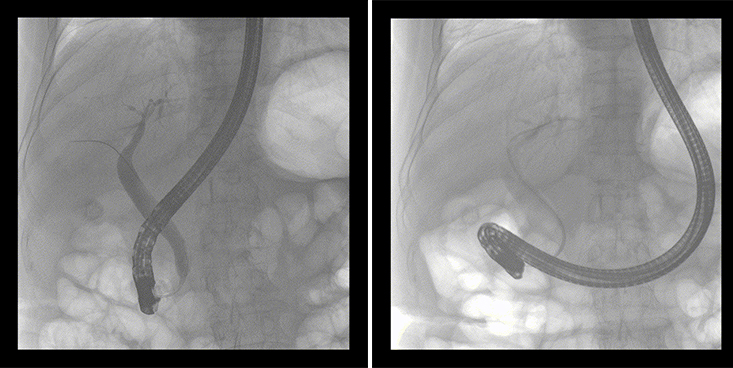

一位86歲的女性患者近來出現(xiàn)腹痛,入院后CT檢查并結(jié)合臨床表現(xiàn)被診斷為急性膽囊炎伴膽囊結(jié)石。經(jīng)專家團隊協(xié)商并與患者家屬溝通,決定對患者實施經(jīng)內(nèi)窺鏡逆行胰膽管造影(ERCP)。

ERCP(經(jīng)十二指腸鏡下逆行胰膽管造影)現(xiàn)已成為比較成熟的微創(chuàng)介入技術,被廣泛的應用于臨床,ERCP也是消化內(nèi)鏡領域難度大、風險大、技術復雜的微創(chuàng)手術,其并發(fā)癥多為致命性,ERCP手術對醫(yī)生的要求很高,因此,ERCP醫(yī)生又被稱為“刀尖上的舞者”。因為手術難度較大,過程復雜,需要C形臂精準的配合,對影像清晰度的要求也非常高。

普愛醫(yī)療移動式平板中C為本次ERCP手術提供實時無損高清影像,幫助醫(yī)生精準定位。“成像效果非常棒!完全不輸國際大牌的醫(yī)學影像設備……”鼓樓醫(yī)院江北國際醫(yī)院內(nèi)鏡中心手術團隊對普愛醫(yī)療移動式平板中C的成像效果給與了高度的評價。

在消化內(nèi)科主任的領導和多科室全力配合下,南京鼓樓醫(yī)院江北國際醫(yī)院成功完成了首例ERCP手術。